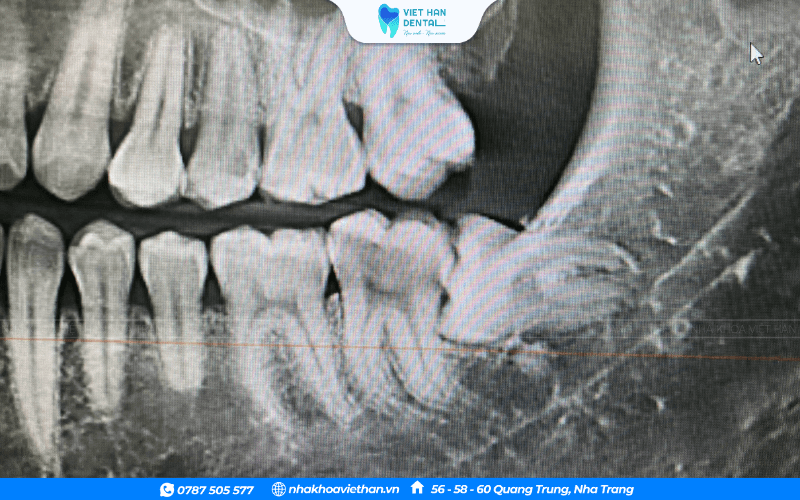

Trước khi tiến hành nhổ răng hàm, bác sĩ sẽ tiến hành chụp X – Quang để xác định được chính xác số chân răng. Thao tác này giúp khách hàng hạn chế tối đa hiện tượng sót chân răng như khi tự nhổ. Tại Việt Hàn, bác sĩ sẽ thực hiện nhổ răng theo đúng quy trình chuẩn của Bộ Y tế.

Trước khi tiến hành nhổ răng hàm, bác sĩ tại Nha khoa Việt Hàn sẽ thực hiện thăm khám tổng quát tình trạng răng miệng, đồng thời khai thác tiền sử bệnh lý của khách hàng một cách cẩn thận. Xác định chính xác số lượng chân răng, hướng mọc cũng như các yếu tố liên quan đến cấu trúc xương hàm. Dựa trên những dữ liệu này, bác sĩ sẽ đưa ra phương án điều trị phù hợp và lựa chọn thời điểm nhổ răng an toàn nhất, giúp hạn chế tối đa rủi ro và biến chứng.

Quá trình nhổ răng hàm tại Nha khoa Việt Hàn được thực hiện theo đúng quy trình chuẩn của Bộ Y tế, với sự hỗ trợ của các thiết bị hiện đại. Trước khi nhổ, bác sĩ sẽ chụp X-quang để xác định rõ cấu trúc răng, từ đó đảm bảo loại bỏ hoàn toàn chân răng, tránh tình trạng sót chân răng như khi tự nhổ tại nhà. Nhờ tuân thủ nghiêm ngặt các bước trong quy trình, việc nhổ răng không chỉ an toàn mà còn giúp rút ngắn thời gian lành thương và hạn chế tối đa biến chứng sau điều trị.